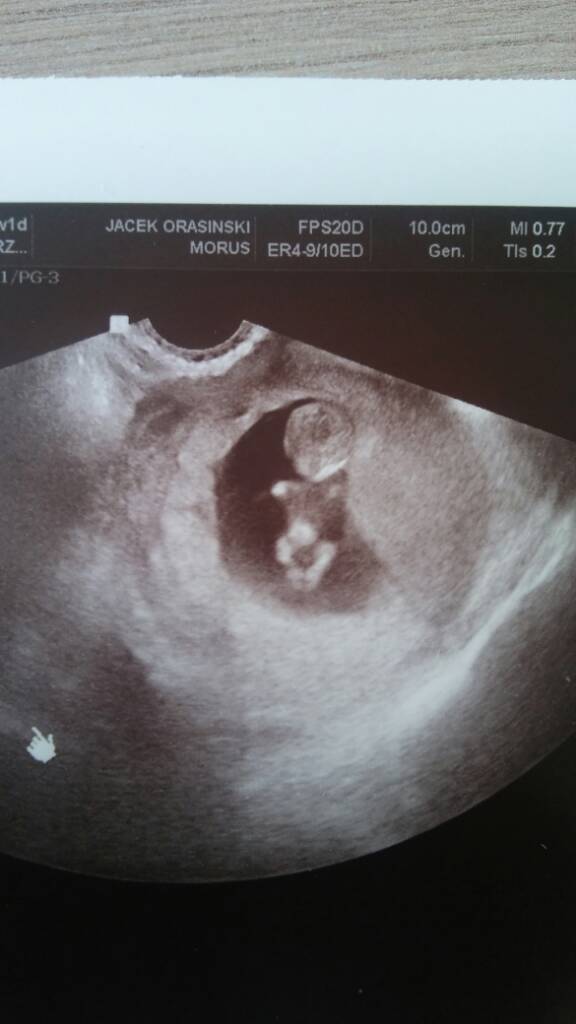

O jaki czaderski ludzik!!!!Hej Dziewczyny ! Na wizycie ulga, i narazie koniec stresu [emoji1]

Zobaczyliśmy nasze cudne Maleństwo, ma już 2,85 cm, wygląda już jak mały człowiek [emoji7] serduszko bije 174 razy na minute [emoji7] Zobacz załącznik 878058

Dokładnie 10t 1d [emoji4]Oooo ja, jaki ludek mały [emoji7] szok. To który dokładnie tydzień teraz masz?

P.s. Tam między nóżkami to tak jakby coś dyndało? [emoji848][emoji13] Ale może mi się wydawac,bo ja to słaba jestem w tych wszystkich plamkach na USG.

Też mi się tak wydaje ale to chyba za wczesnie [emoji4]

Chyba za wcześnie na to [emoji1]Ale extraA ten mały człowieczek klejnoty pokazuje chyba

Aaaa tam, dla mnie chłopak jak nicDokładnie 10t 1d [emoji4]